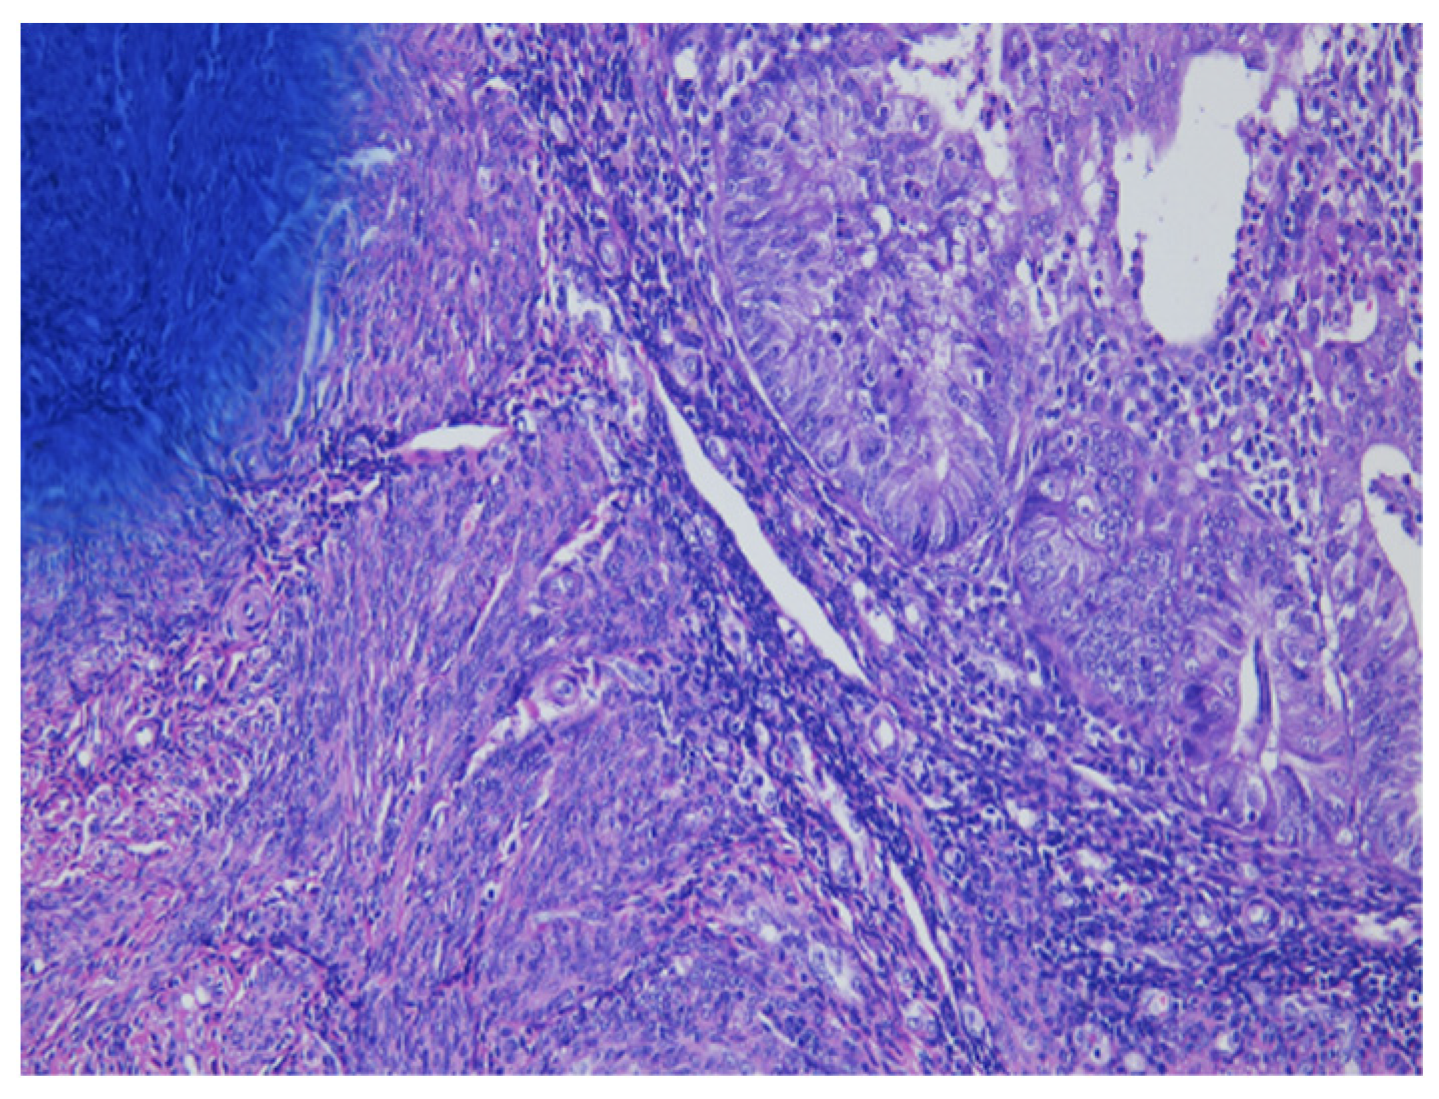

As shown in Figure 1 of EC at the uterine cornus, negative MI was found with an intact thin rim of stroma between the tumor–myometrium junction on the left side and with positive MI featuring an absence of stroma between the junction on the right side. A further higher power scope of the left side and right side of Figure 1 is shown in Figure 2 and Figure 3, respectively. Figure 2 demonstrated a thin rim of endometrial stroma between the tumor-myometrium junction (dark blue area: dark blue nuclei of stromal cells), and Figure 3 revealed the superficial early MI. MI determined by histopathology was the gold standard for comparison.

Figure 2.

Thin rim of endometrial stroma between tumor–myometrium junction means no myometrial invasion (200× magnification).